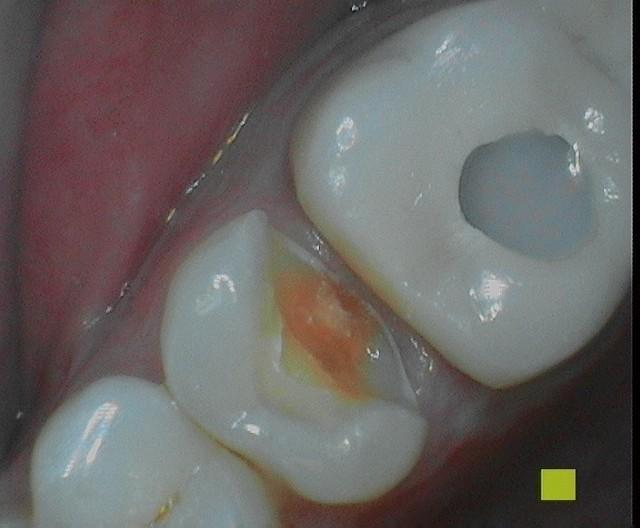

Chipped old filling with recurrent decay was restored with Porcelain Inlay in less than 2 hours. No second visit!